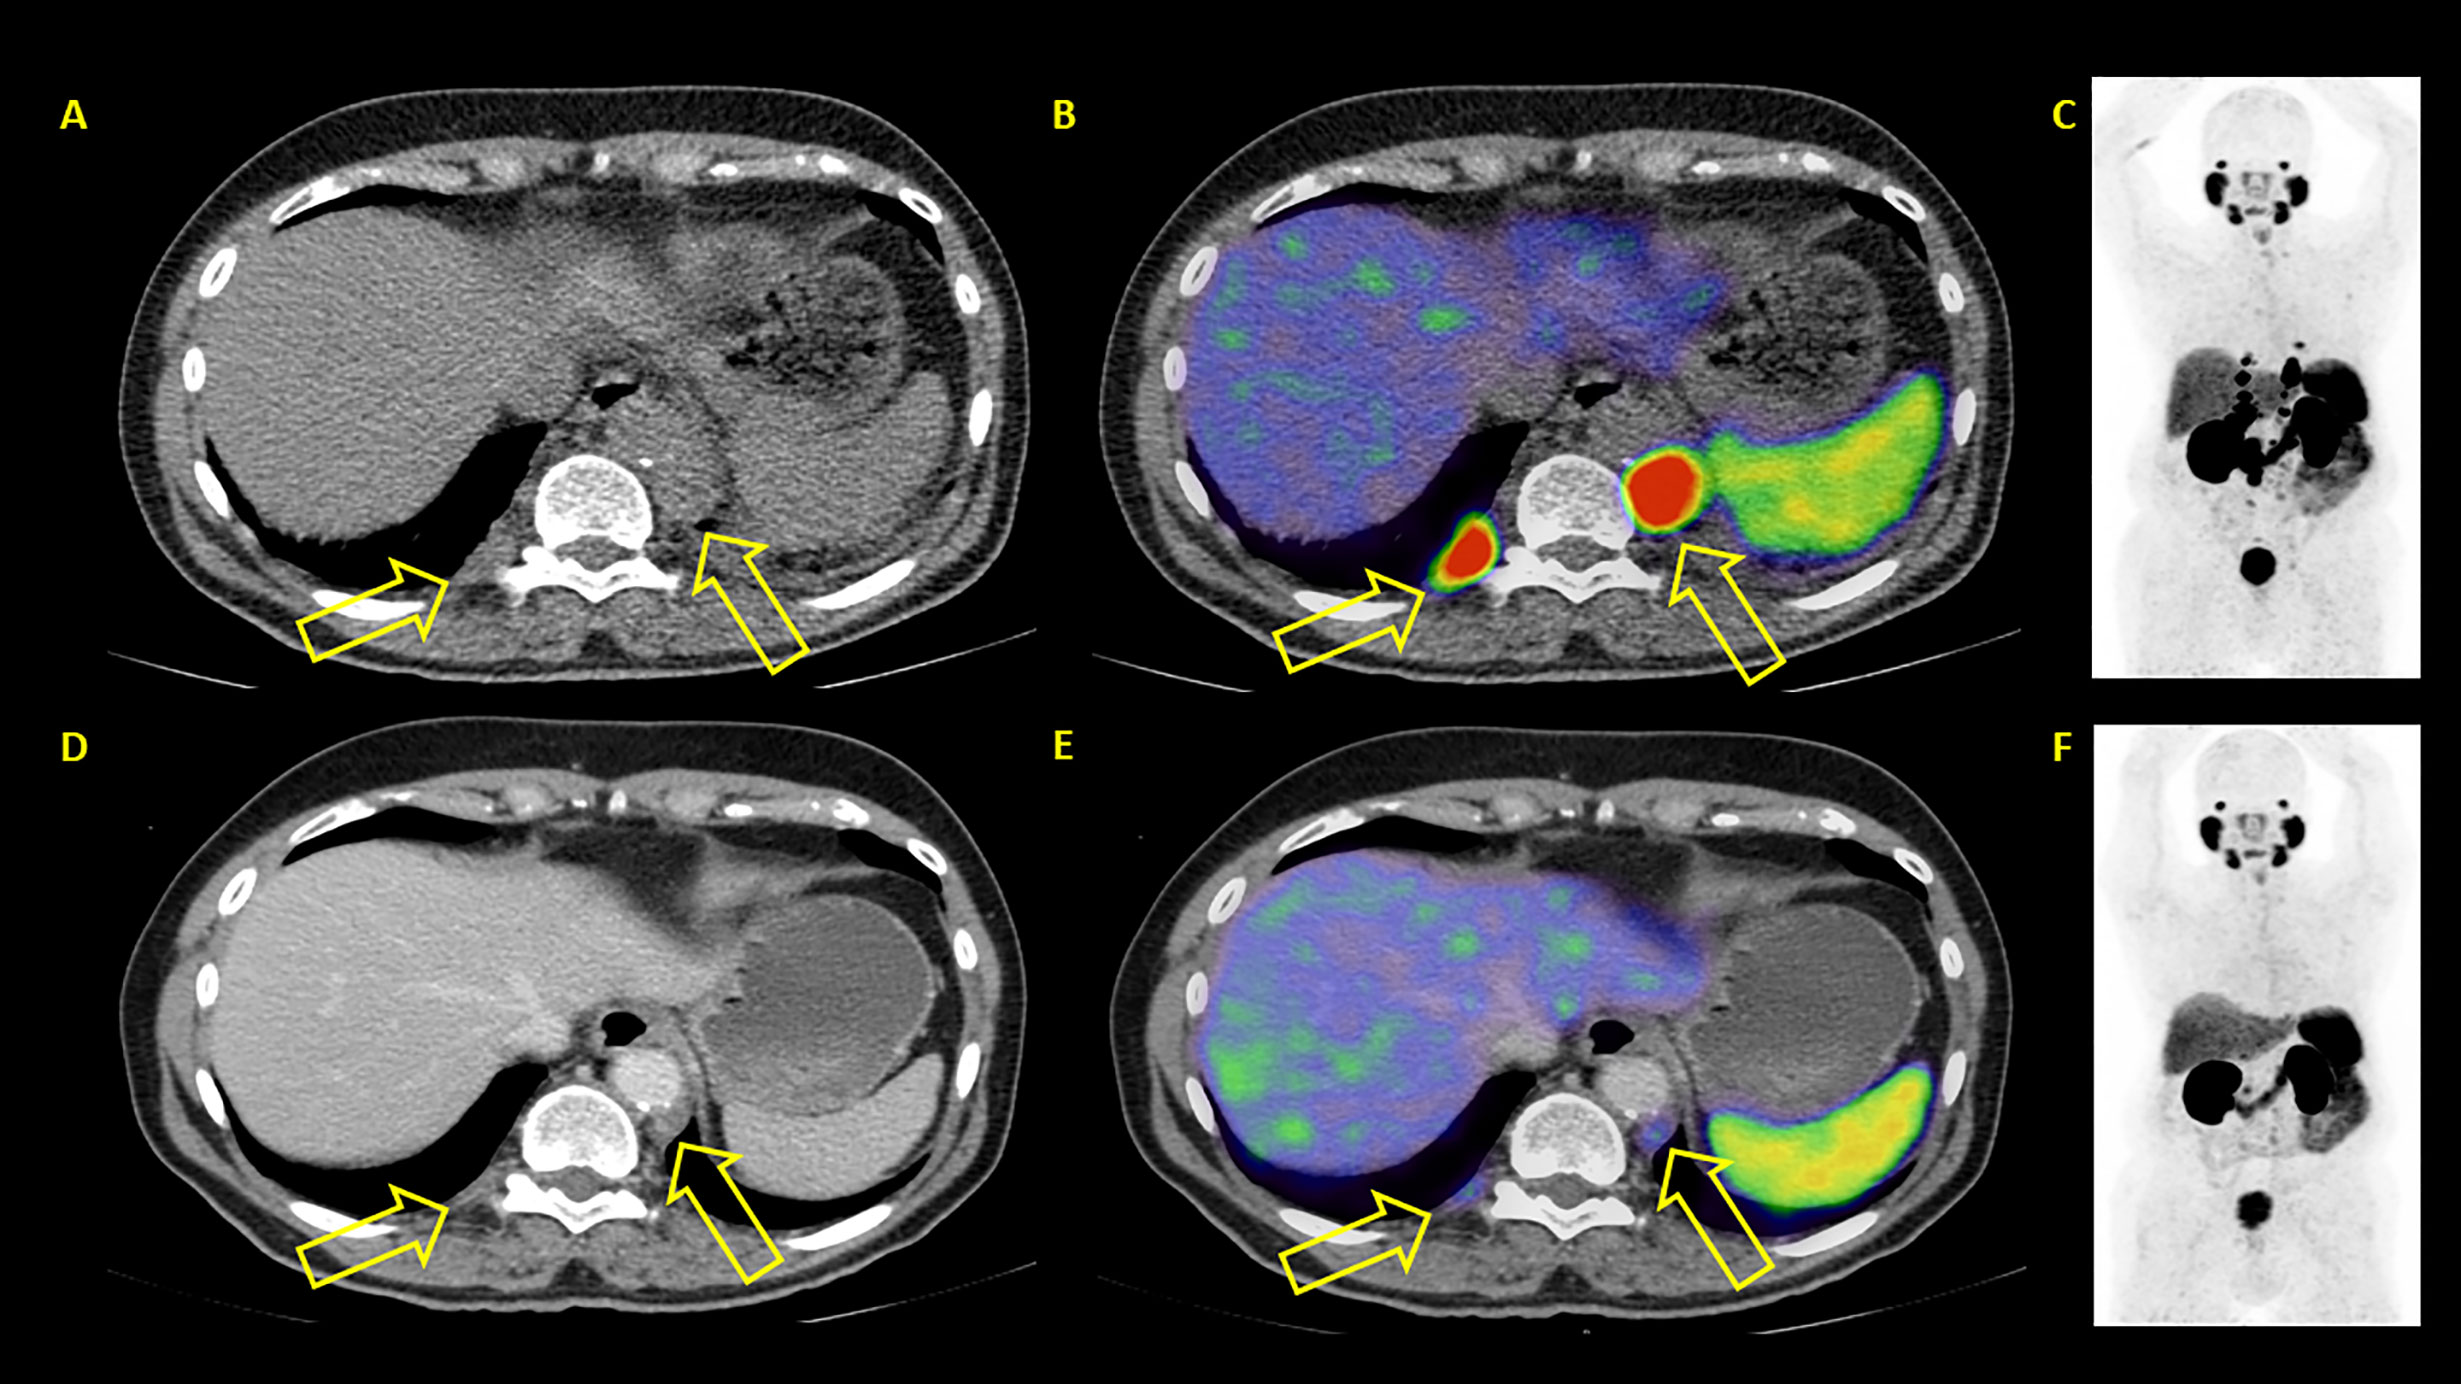

In contrast to PSA response, PSMA PET/CT based response evaluation showed objective response (52.6% PR and 23.7% SD) in about three-fourths of the patients and PD in 23.7%. Figures 5–7 show examples of patients showing concordant and discordant results between PSA and RLT-REC-PCA response. Fendler et al. reported similar results with PR in 27%, SD in 40% (objective response 67%) and PD in 33% of patients based on 68Ga-PSMA PET/CT response assessment in 15 patients after two treatment cycles (19). A direct comparison of our results with previously published data is hampered by the fact that our image based response analysis was based upon RECIST 1.1 with integration PET data for bone metastases assessment whereas Fendler et al. used only measurable CT based assessment excluding bone lesions (16).

Figure 5 (A) Example of a patient where both PSA and PET showed similar results: progressive disease. After two therapy cycles PSA values increased from 93.2 to 214.2 ng/ml. PET/CT showed new bone lesions as well progression of previously known lesions. (A–C) represent baseline images whereas (C–E) represent interim PET/CT. (A, D): axial CT slices; (E): axial fused PET/CT images; (C, F) maximum intensity projection images. (B) Example of a patient where both PSA and PET showed similar results: progressive disease. After two therapy cycles PSA values increased from 327 to 1467 ng/ml. PET/CT showed diffuse new bone lesions. (A–C) represent baseline images whereas (C–E) represent interim PET/CT. (A, D): axial CT slices; (B, E): axial fused PET/CT images; (C, F) maximum intensity projection images.